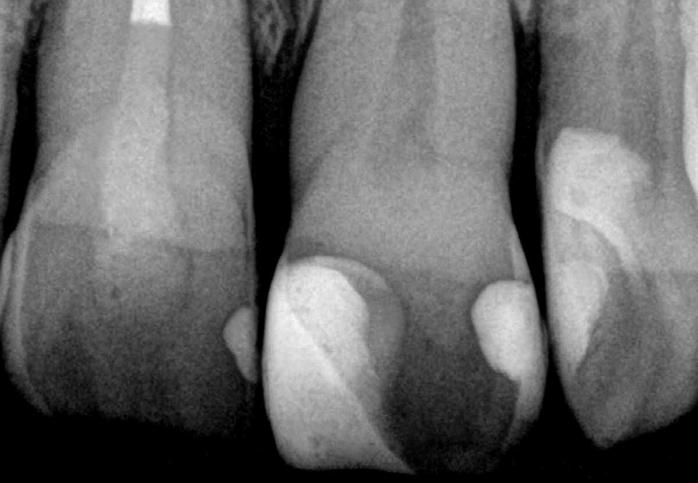

G-ænial A’CHORD Images courtesy of J. Tapia Guadix, Spain Images courtesy of Dr W. Boujemaa, France Images courtesy of Dr G. Benjamin, Germany G-ænial A’CHORD veneer on tooth 11 Near-UV 405 nm initial situation Conventional composite veneer on tooth 11

Radiopacity (318 % Al) optimizes the radiographic follow-up over time.

Image courtesy of Dr W. Boujemaa, France